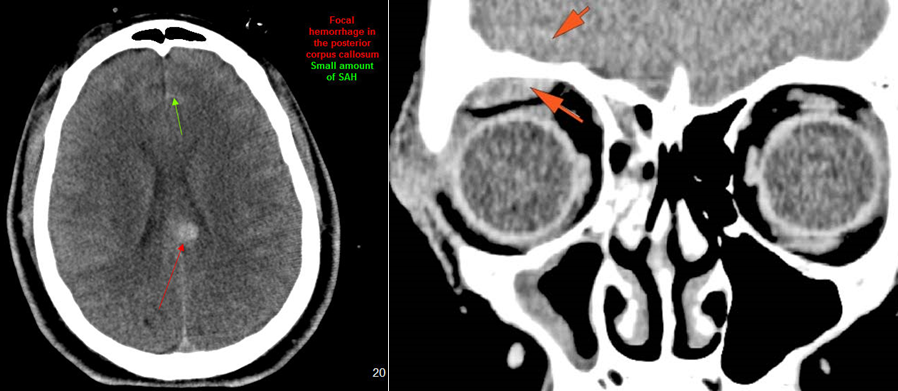

Intracranial

There is subperiosteal, epidural or subdural hematoma and/or pneumocephalus along the boney walls of the anterior or middle cranial fossa or elsewhere. [Yes/No]

There is subarachnoid bleeding. [Yes/No]

There is evidence of parenchymal brain injury. [Yes/No]